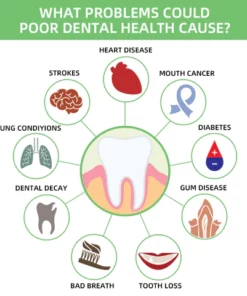

What Problems Could Poor Dental Health Cause?

- Oral diseases, while largely preventable, pose a major health burden for many countries and affect people throughout their lifetime, causing pain, discomfort, disfigurement, and even death.

- It is estimated that oral diseases affect nearly 3.5 billion people.

- Untreated dental caries (tooth decay) in permanent teeth is the most common health condition according to the Global Burden of Disease 2019.

- Treatment for oral health conditions is expensive and usually not part of universal health coverage (UHC).

- Most low- and middle-income countries do not have sufficient services available to prevent and treat oral health conditions.

- Oral diseases are caused by a range of modifiable risk factors common to many noncommunicable diseases (NCDs), including sugar consumption, tobacco use, alcohol use poor hygiene, and their underlying social and commercial determinants.